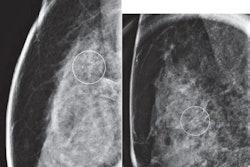

Detecting breast arterial calcifications on routine mammograms could identify women at a higher risk of future cardiovascular disease (CVD), a study published March 13 in Clinical Imaging found.

Breast arterial calcifications are incidental findings on mammograms. While previous studies have suggested an association between these findings and cardiovascular diseases, questions remain about the clinical utility of reporting them and managing of women who have these calcifications on mammography.